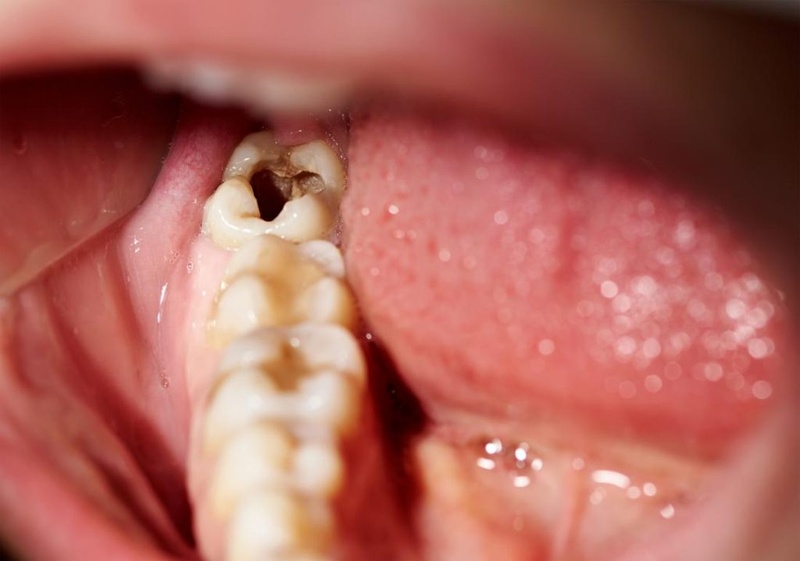

- Bệnh lý răng miệng: Vì răng khôn nằm sâu trong cung hàm nên rất khó vệ sinh sạch sẽ. Vi khuẩn, vụn thức ăn rất dễ đọng lại ở vị trí này, làm tăng nguy cơ mắc các bệnh lý khiến răng khôn bị mẻ vỡ.

III. Răng khôn bị mẻ có cần phải phục hình lại không?

Riêng với răng khôn bị mẻ, bác sĩ thường khuyên bệnh nhân nên nhổ đi. Nguyên nhân là do:

- Việc vệ sinh răng khôn là khá khó khăn, nguy cơ cao gây nhiều bệnh lý răng miệng.